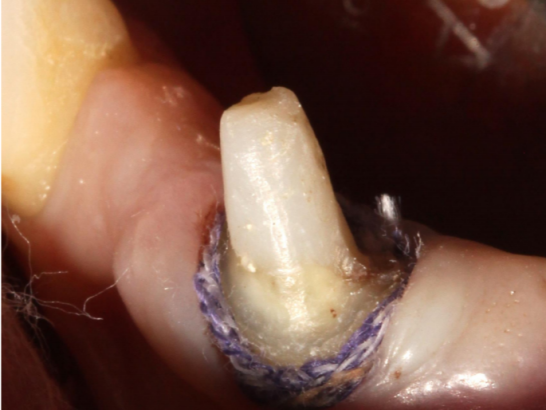

ステップ2: 最初の引き込みコードを歯肉溝に置きます

歯肉引き込みコードのモデルは、歯肉溝の1/2を満たす能力に基づいている必要があります。 最初の収縮コードは、歯肉組織を損傷から保護するのに役立ち、接合部の上皮付着部位を特定するのにも役立ちます。

ステップ4: 2番目の引き込みコードを歯肉溝に置きます

歯肉溝を埋める引き込みコードを選択します。 引き込みコードが歯を完全に取り囲むことが観察され得る。 第2の引き込みコードは、しばしば止血材料を含浸させる必要がある。

ステップ5: 2番目の引き込みコードを取り外します

出血状況、水の制御、および完全な肩のエッジラインが見えるかどうかを評価します。